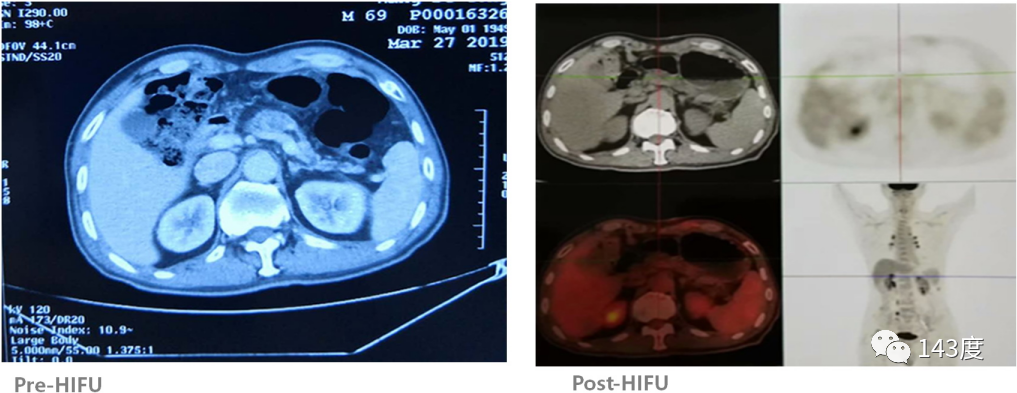

Pancreatic Cancer Treatment Case 6:

Patient: Male, 69 years old, pancreatic cancer

A follow-up PET-CT scan half a month after HIFU treatment revealed complete disappearance of the tumor, no FDG uptake, and a subsequent decline in CA199 levels.